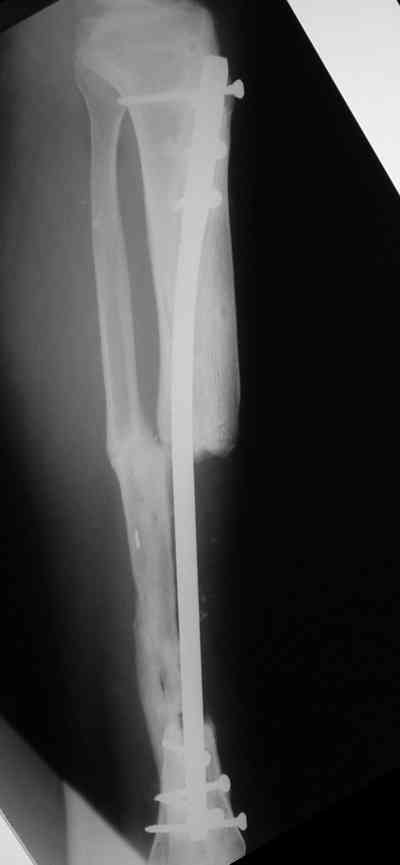

Владимир, свободная костная пластика на фоне свища вряд ли оправдана. Почему не рассматриваете вариант транспорта кости по Илизарову? Что собираетесь делать с латентной инфекцией? Одни антибиотики не помогут, необходима полноценная хирургическая обработка, Мы бы подумали о цементном спейсере с антибиотиками, бусах. После купирования инфекции переходить к замещению

дефекта: за счет удлинения концов б\б кости или тибиализации м\б. На начальном этапе фиксация только в аппарате, в последствие для удержания достигнутого можно перейти на фиксацию интрамедуллярным штифтом (см. вложенные файлы)

Как дополнение высылаю снимки и фото конечности, чтобы Вы могли оценить состояние м/т, и течение заболевания.

А доклад из Германии, действительно, был интересный. Правда пока у авторов немного наблюдений. И еще прозвучала мысль, этот метод не предназначен для применения при наличии проявлений инфекции. Прилагаю несколько иллюстраций (1 - вид кейджа во время операции перед закрытием лоскутом на свободной ножке, 2 - рентгенограммы через 32 месяца после операции, 3 - слайд, перечисляющий преимущества методики).

Одно маленько добавление. У одной пациентки с большим, но еще неокрепшим регенератом большеберцовой кости мы установили подобный спейсер. Она уехала в свой родной город, где врачи демонтировали ей спицстержневой аппарат, фиксировавший сегмент. Но при нагрузке регенерат чуть деформировался. Через 4 месяца уже у нас в институте при удалении спейсера загнутый в виде колечка кончик спицы при тракции разогнулся и мы помучились с удалением, так как зацепиться за спейсер было невозможно. Теперь загибаем спицу несколько иначе (рис. 4).